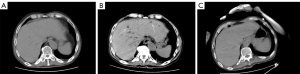

Despite stepwise anti-infection treatments, a follow-up CT on the 14th revealed HPVG with terminal ileal edema (Figure 6). Emergency exploratory laparotomy confirmed extensive intestinal necrosis, extending from 80 cm distal to the ligament of Treitz to the ascending colon. A radical intestinal resection was performed, leaving a residual small intestine of less than 50 cm, followed by a jejunostomy. By Day 28, with eosinophil counts normalized, the steroid regimen was gradually tapered: prednisolone was first reduced to 10 mg three times a day over 7 days, and the patient was then transitioned to dexamethasone (5 mg) once daily to minimize adrenal suppression.

HPVG formation in HES follows a “three-level cascade”: (I) eosinophil toxic proteins (major basic protein and eosinophil peroxidase) damage the intestinal mucosal barrier and induce microvascular spasm; (II) aerogenic bacteria infiltrate the portal system through the compromised mucosa; and (III) ischemia-reperfusion injury increases intestinal permeability, allowing gas entry into the bloodstream. A 10-day interval separated the initial abdominal pain (Day 4) and HPVG appearance (Day 14). CT imaging during this period revealed no mesenteric vascular occlusion, suggesting microcirculatory embolism predominance. This highlights the need for an “HES intestinal ischemia risk score” to improve early detection.